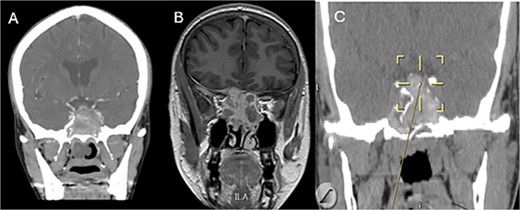

A 36 years-old man with no previous history of medical disease presented to the otolaryngology clinic with a chief complaint of headache that was associated with pressure feeling mainly in the occipital area. He also reported a post-nasal drip. The patient underwent a non-contrast paranasal sinus CT scan (Fig. 1) that demonstrated an isolated sphenoid sinus homogenous opacification, most likely representing sphenoid fungal ball. A decision was made to proceed with endoscopic sphenoidotomy (Fig. 2) to clean and remove the debris, which confirmed the diagnosis of sphenoid sinus fungal ball.

Coronal (A) and axial (B) images of a nonenhanced CT scan of the paranasal sinuses showing left sphenoid sinus complete homogenous opacification.